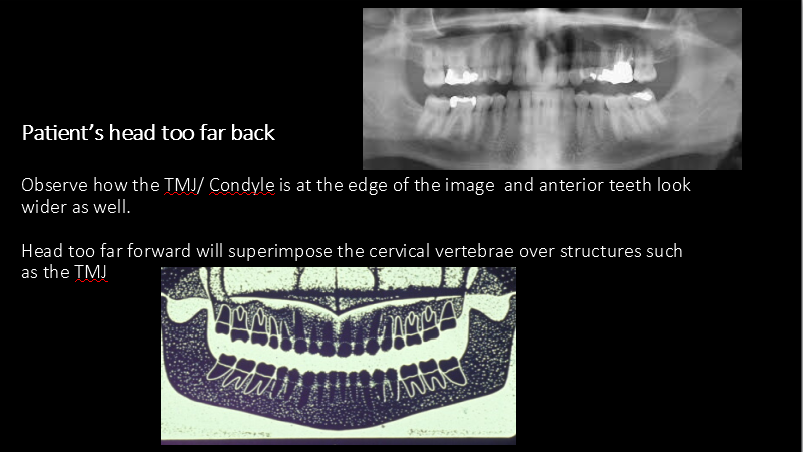

Error: patient too far foward

Error: patient too far back

What errors are these?

What error is this?

Error: slumped position/vertical spine shadow

Error: improper tongue position